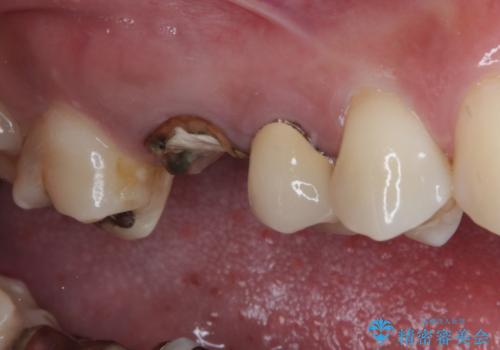

詰めている材料を外したところ、目視で確認できるほど割れており、要抜歯との説明をし、インプラント治療を行うこととしました。

骨量が十分にあることが3次元CTより確認されたため、事前に仮歯を用意した上で、抜歯即時埋入インプラントによる補綴治療を行うこととしました。

来院されるまではインプラント治療を躊躇されていましたが、抜歯即時埋入により、単回の外科処置で治療が終えられることのメリットを理解され、インプラントによる補綴治療を行いました。